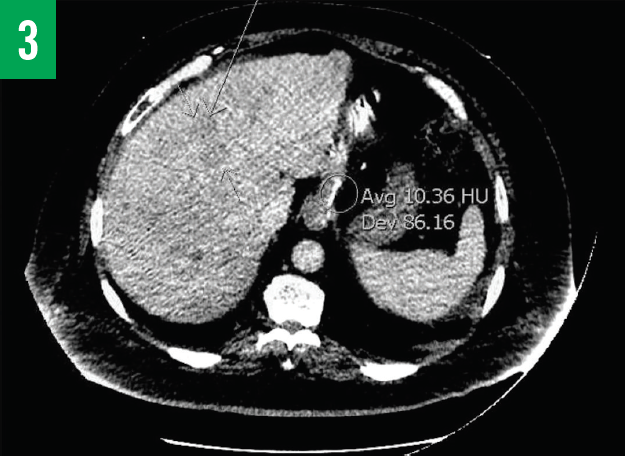

Computed tomography (CT) scans of the chest and abdomen/pelvis showed innumerable low-attenuation lesions scattered throughout the liver, with the largest measuring up to 5.5 cm in diameter (Figures 1A-1C); the lesions were likely related to metastasis. A questionable lesion was also noticed at the head of the pancreas (Figure 2), and the scan showed bowel-wall thickening involving the proximal descending colon (Figure 3).

Figure 3. CT scan of the abdomen/pelvis showing numerous low-attenuation lesions scattered throughout the liver and bowel thickening involving the proximal part of the descending colon.